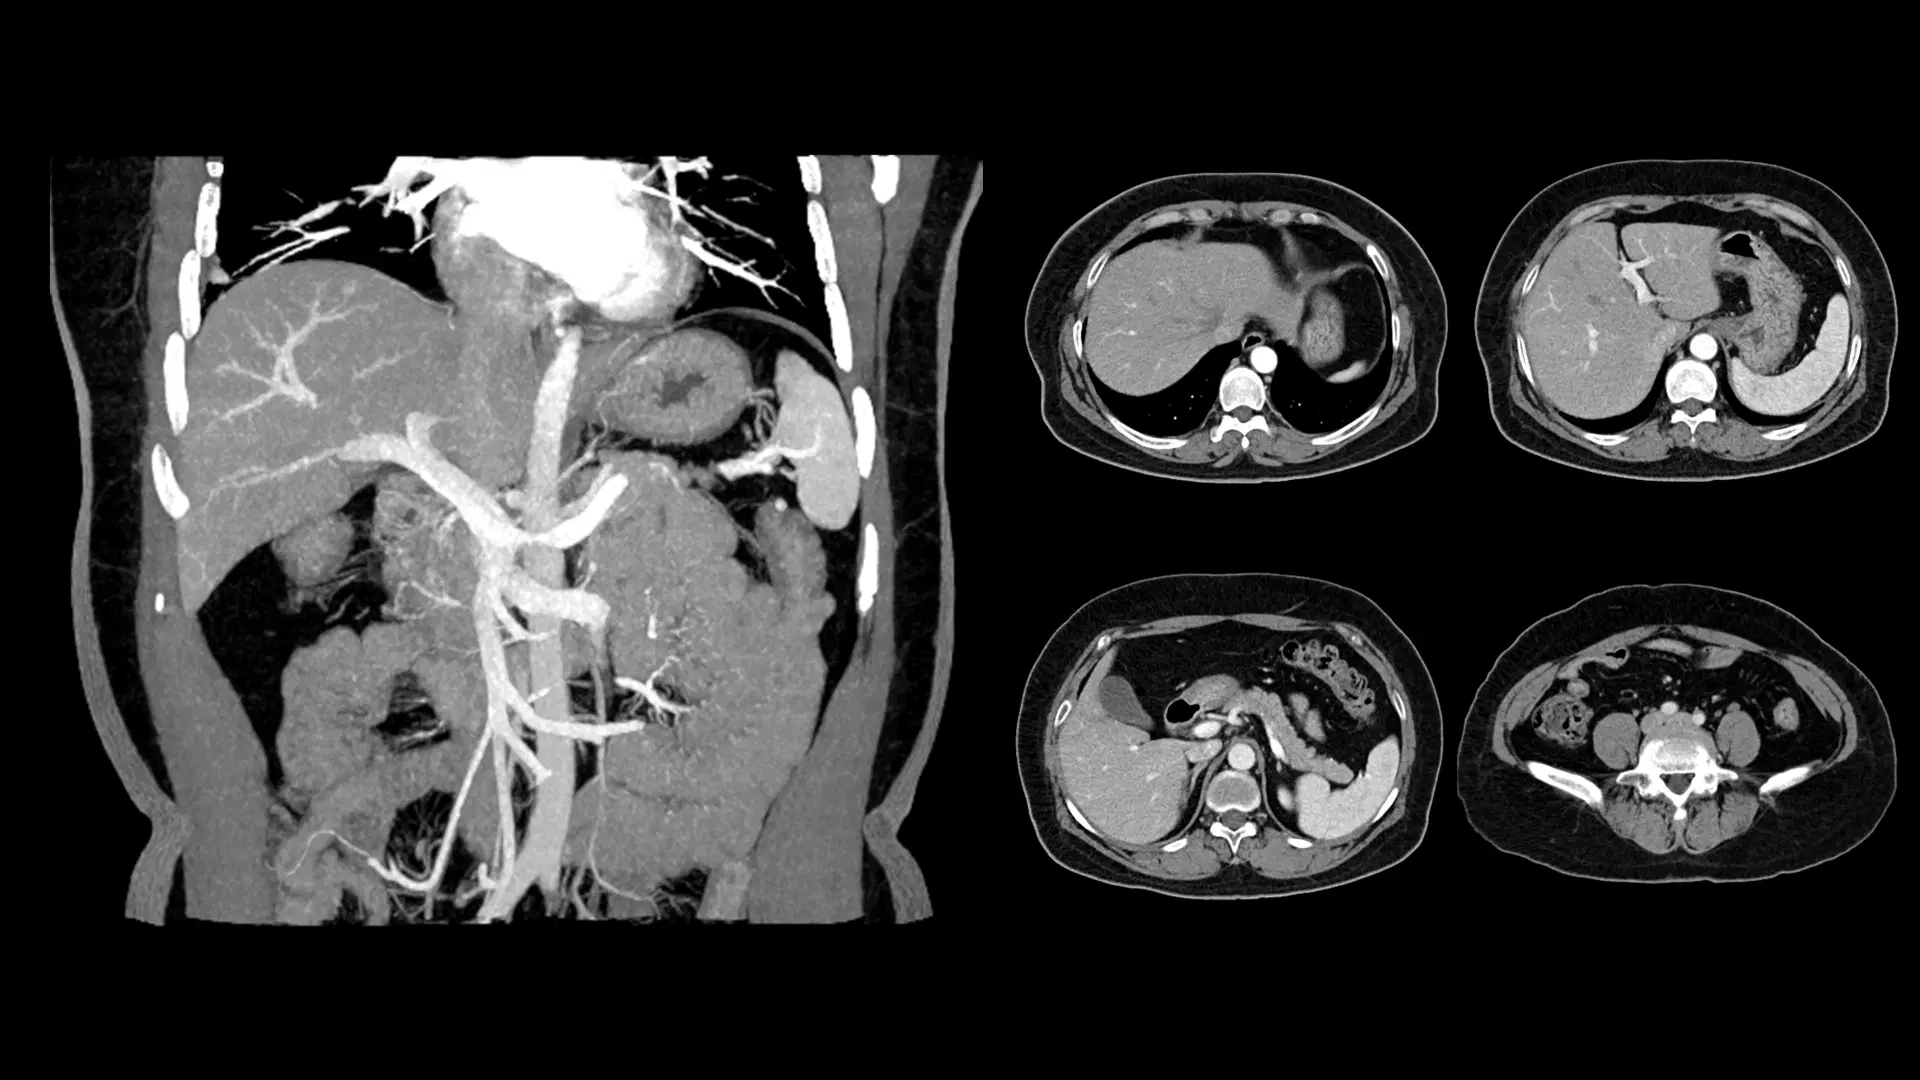

Abdomen & Pelvis CT Internal Organ Assessment Evaluates liver, kidneys, pancreas, spleen, and reproductive organs.

CT Angiography (CTA) Blood Vessel Visualization Detailed images of arteries and veins to detect blockages or aneurysms.